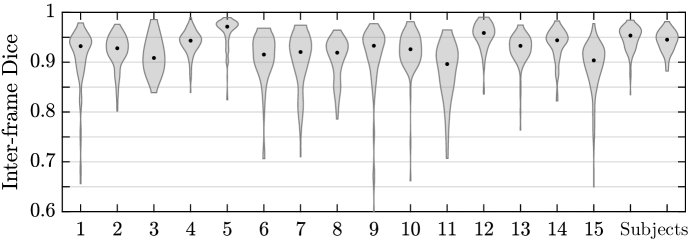

Table 3 presents statistics of the consistency between predicted label maps in consecutive volumes of the MRI time series. Predictions are highly consistent, achieving a Dice of . The small differences between the relative mean-BOLD values suggest these produced segmentations may be suitable for research studies assessing placental function.

Fig. 4 presents distributions of Dice score between predicted label maps of consecutive frames in the BOLD time series. Distributions have high medians () for all but one case, with wide density at high Dice scores (. Dice differences are highly affected by fetal and maternal motion that causes placental deformation. We visually verified that modest drops in Dice () were mainly due to fetal motion, but large drops (Dice ) resulted from errors in the produced label maps.

We assessed the consistency of predictions in BOLD MRI time series using our model, and achieved highly consistent predictions (Dice ). For many subjects, we observed modest drops in Dice (), which were often due to fetal motion displacing the placenta. However, in a small number of cases, we observed large drops (Dice ) that we visually verified were caused by segmentation error. Since we apply the model to each volume in the time series independently, imaging artifacts, such as intensity and geometric artifacts, can affect the predicted segmentations. In future work, we will investigate incorporating temporal consistency between consecutive volumes. We will also investigate applying test-time augmentation on image intensity as this has been shown to reduce uncertainty and improve segmentation robustness [22].